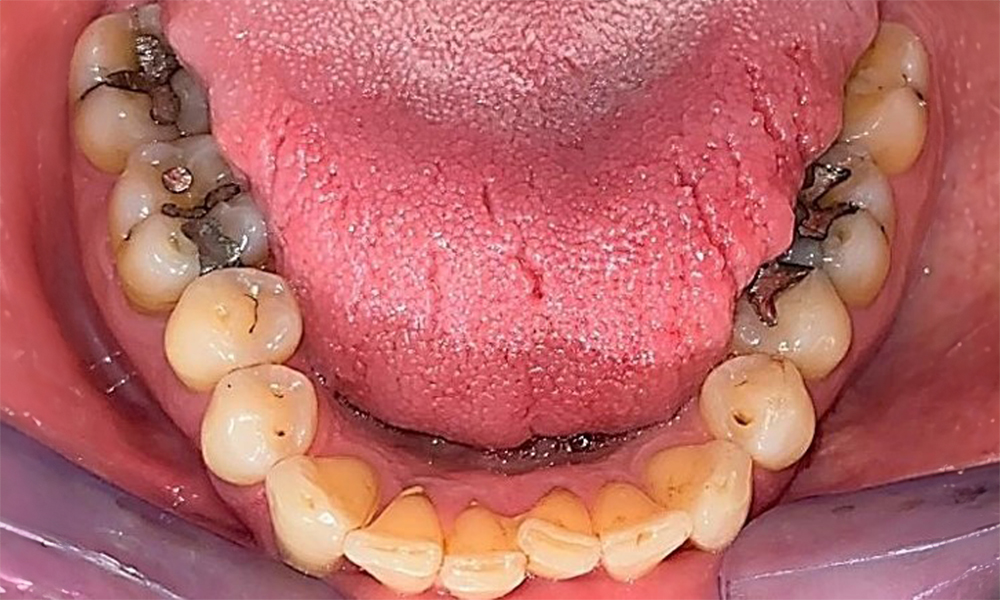

Зъбни резултати

Пациентът има пълно съзъбие с 28 зъба, което включва амалгамни и композитни пломби в областта на моларите и премоларите. На зъб 14 има видима клинична маргинална празнина. Зъб 27 има адекватна златна инкрустация. Налице са и генерализирани атриции и абразии. (фиг. 2, фиг. 3, фиг. 4, фиг. 5, фиг. 6)

Пациентът е с пародонтит II стадий, степен В (5). Клиничните дълбочини на сондиране от 1 до 3 mm са във физиологичния диапазон. Локализирани дълбочини на сондиране от 5 mm са наблюдавани медиопалатинално на 17 и 27. Налице са генерализирани рецесии от 1 до 3 mm с частична загуба на интердентални папили (фиг. 2, фиг. 3, фиг. 4)

Пациентът използва интердентални четки и електрическа четка за зъби и спазва добра орална хигиена у дома. Редовната мотивация и повторното обучение са задължителни поради риск от прогресия, особено по отношение на почистването на междузъбните пространства, тъй като в тези области е установена повишена дълбочина на сондиране. В лингвалната област на долната челюст има локализиран зъбен камък и мека плака и те трябва да бъдат показани на пациента. Може да се наложи да се провери и коригира размерът на интерденталните четки. Въз основа на наличието на открити коренови повърхности се препоръчва мека приставка на четката, за да се предотвратят клиновидни дефекти. Трябва да се използва паста за зъби с ниска абразивна стойност.